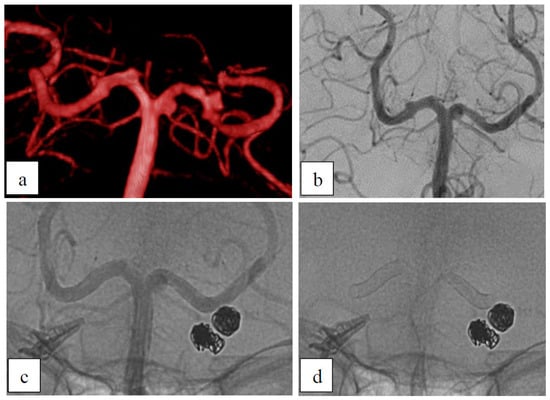

Case 2: Dysplastic Aneurysm with Incorporated Branch

| 2 | 55 | f | A2 (two aneurysms) | right | dysplastic | no | no | ASA+ Prasugrel | prox: B2 dist: A2 | prox: 6 dist: 6 | prox: D1 dist: B2 |